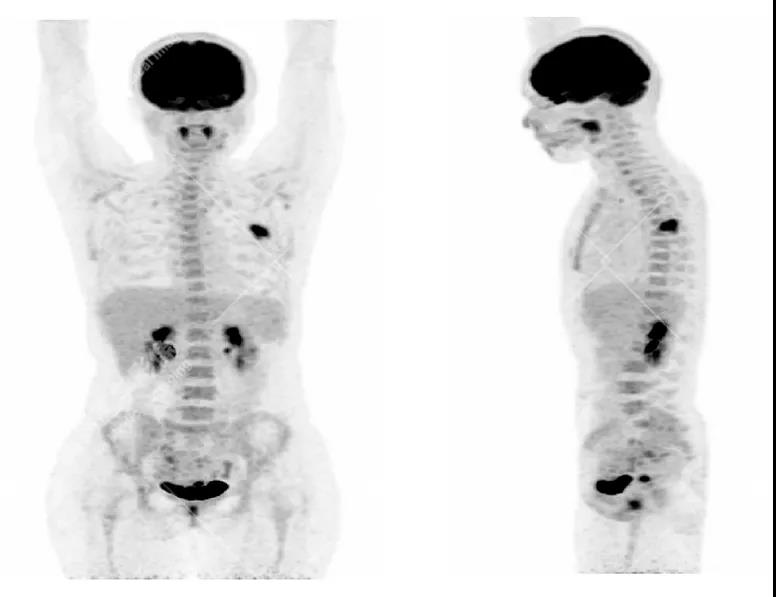

• 根據(jù)WHO統(tǒng)計(jì),在女性惡性腫瘤中排名第一、二位的是乳腺癌和宮頸癌,而且越來(lái)越年輕化的趨勢(shì)。

• 本次兩個(gè)案例均因單發(fā)骨質(zhì)破壞病灶引發(fā)的骨痛查體,相應(yīng)原發(fā)病灶并無(wú)相應(yīng)臨床癥狀,病灶也不大,若是局部分析,診斷容易受限,難以鑒別。

• PET/CT全身排查的優(yōu)勢(shì)在于發(fā)現(xiàn)其它部位隱匿病灶,鑒別原發(fā)與轉(zhuǎn)移灶,提示臨床,得到病理學(xué)支持,這樣能精準(zhǔn)的診斷,從而進(jìn)行下一步有效的治療。